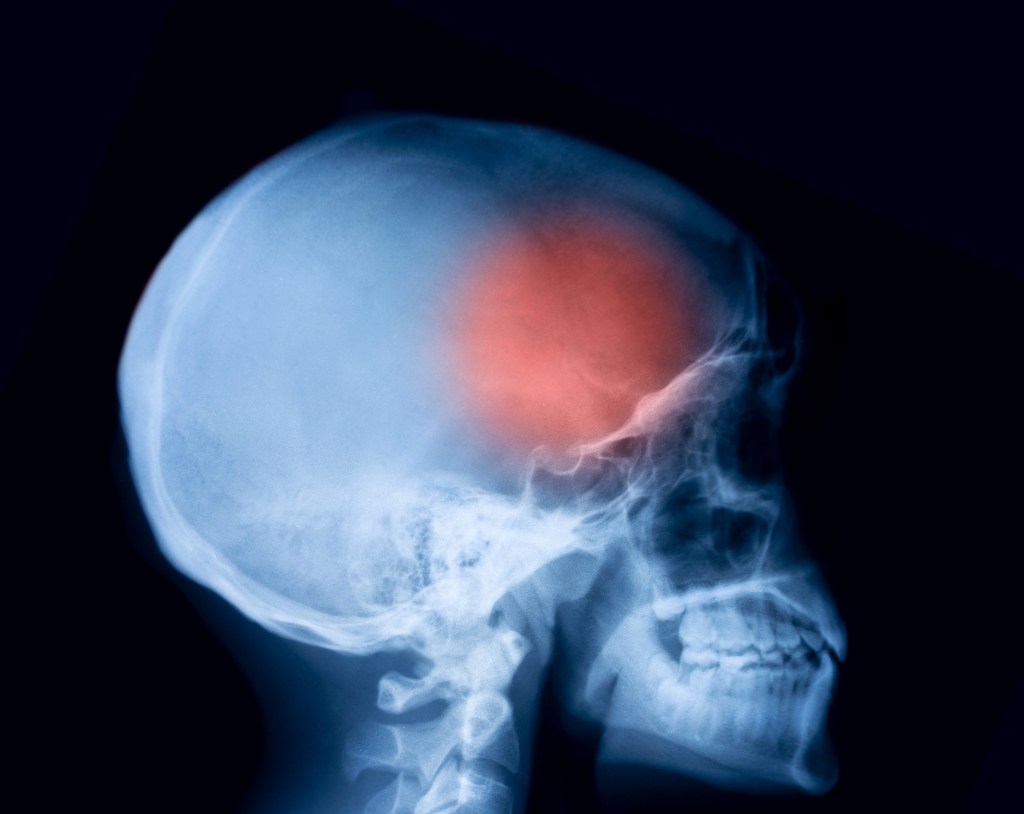

Tras un traumatismo craneal lo más habitual es que se quede todo en un susto y no sea más que una herida o un chichón. Pero en alguna ocasión puede complicarse y presentar otros problemas como la conmoción cerebral, una fractura craneal o un sangrado cerebral (de ahí la importancia de conocer los signos de alarma).